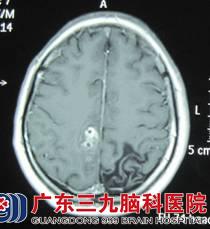

小邓,19岁,右手发作性抽搐已有15年,通过检查,CT及MRI的结果提示:右侧顶叶深部白质内病灶,血清裂头蚴抗体呈阳性。神经外六科的吴杰主任诊断为:1、症状性癫痫,2、右侧顶叶中央区脑裂头蚴病。

术前颅内影像